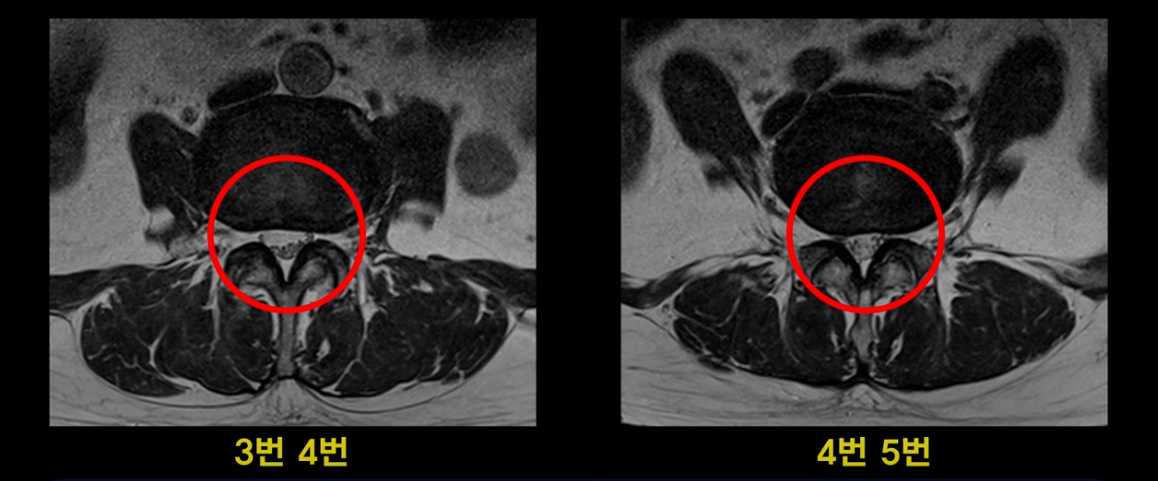

이분 MRI를 보면 여러 마디가 퇴행이 진행되어 있고

3번 4번과 4번 5번에 중심성 협착이 있는데

4번 5번이 더 심합니다.